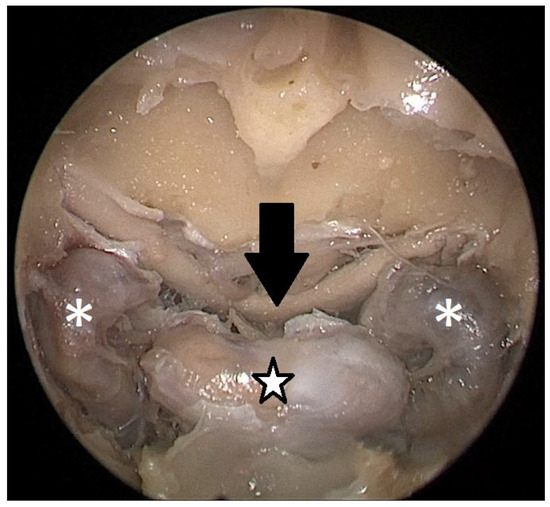

Cadaver pituitary surgery: On each of the two cadaveric heads, we used the paraseptal binostril approach for the sphenoid sinus. A 30° Storz endoscope (Karl-Storz, Austria, Vienna) was used. The head was mounted in a Mayfield cranial stabilization device. The surgery started with a lateralization of the inferior and medial turbinates. The anterior sphenoid wall and ostium to sphenoid sinus were identified. Using the straight suction with a marked scale, 1 cm and 2 cm distances from the anterior sphenoid wall were measured and marked with a scalpel on the posterior part of the septum. Using a scalpel, Kerrison punch, and backbiter punch, a posterior septal resection 1 cm from the anterior wall of the sphenoid was performed. We continued with the wide opening of the sphenoid cavity and resection of the intersphenoidal septum and the full exposure of the posterior wall, both ICAs, and optocarotic recesses (OCR). The posterior wall of the sphenoid sinus and dura were resected to better identify anatomic landmarks, with both ICAs, pituitary gland, chiasma, and optic nerves visible at the end of a resection (Figure 4). The straight suction was inserted into the sphenoid sinus so that the instrument’s tip was in the most lateral position in the sphenoid sinus without infracturing the rest of the nasal septum. A picture was taken in this position to evaluate the most lateral part of the sphenoid sinus that could be reached with a straight instrument with a 1 cm septal resection without infracturing the nasal septum (Figure 5). Enlargement of the septal resection to 2 cm from the anterior sphenoid wall was performed with a backbiter punch and scalpel. The straight suction was inserted into the sphenoid sinus so that the instrument’s tip was in the most lateral position in the sphenoid sinus without infracturing the rest of the nasal septum. A picture was taken in this position to evaluate the most lateral part of the sphenoid sinus that could be reached with a straight instrument, with a 2 cm septal resection, without infracturing the nasal septum (Figure 6).

Figure 4. Opened sphenoidal sinus, endoscopic view, fully exposed ICAs (white asterisks), pituitary gland (black and white star), and optical chiasm (black arrow).